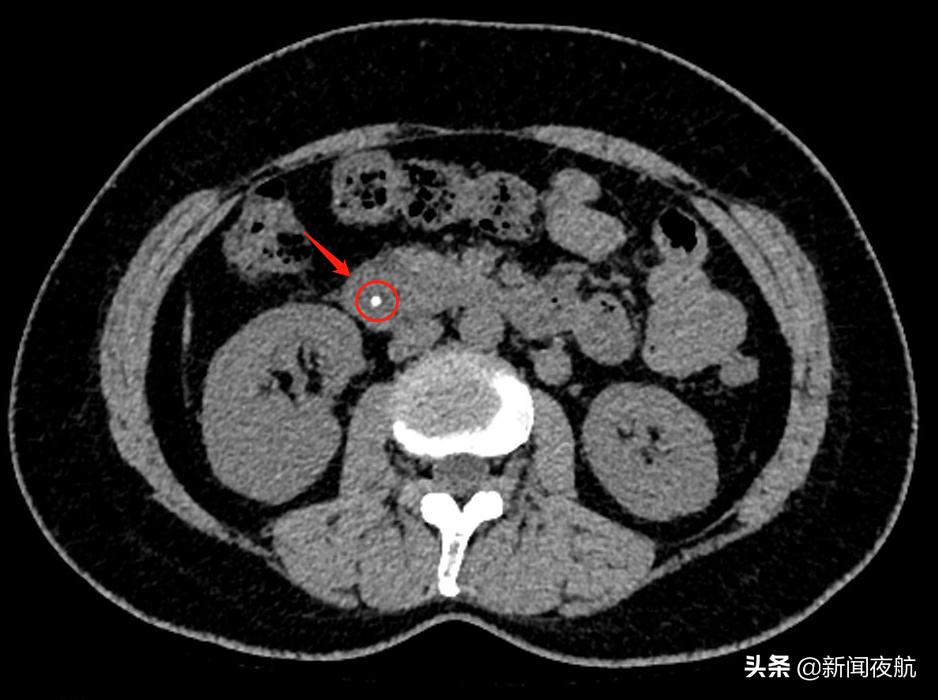

经过了CT检查,很快就找出了原因——胆总管卡着一颗大小约4mm的“石头”。这个石头卡在胆汁与胰液的出口处,让程女士出现腹痛。

程女士的CT片子